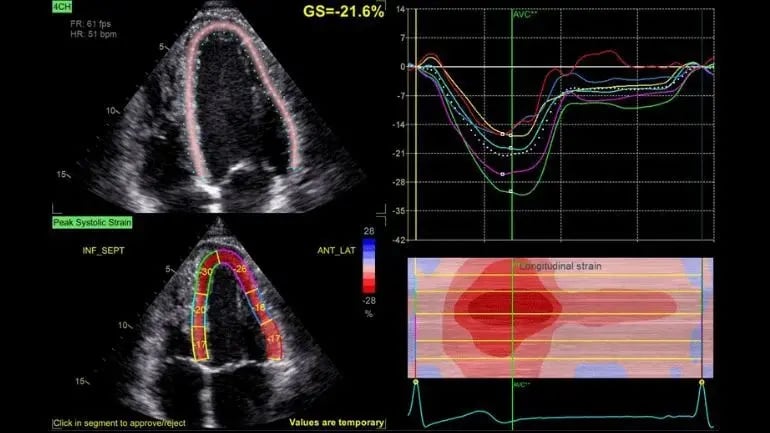

• Ecocardiograma en reposo 2D, 3D, 4D, con strain rate, tisular, sincronía cardiaca.

Ecocardiograma con análisis de deformación miocárdica y gráficos cardiacos

• Ultrasonido Vivid 9 de GE con Strain Rate y sonda 4D Holter y MAPA Spacelabs y GE.